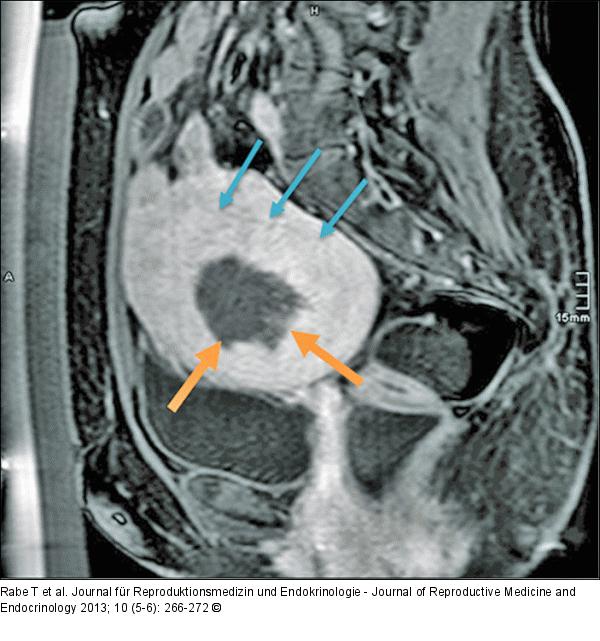

Abbildung 3c: HIFU-Behandlung Sagittale Kontrastmittel-MRT (T1-gewichtet) direkt nach HIFU-Behandlung mit Nachweis des zentralen, hypointens zur Darstellung kommenden Perfusionsdefektes des Myoms (orange Pfeile). Differenzierung der Kapsel des submukös-intramuralen Myoms vom normalen Myometrium durch eine feine Trennschicht (blaue Pfeile). |